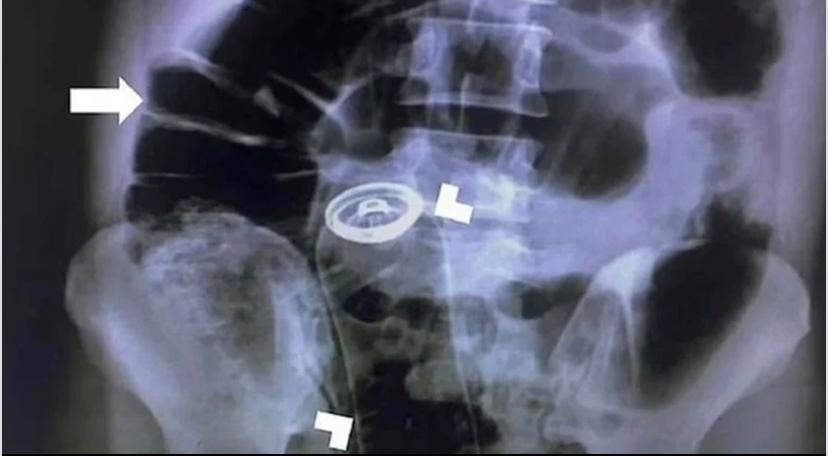

Mədəsində bir qutu dezodorant tapıldı